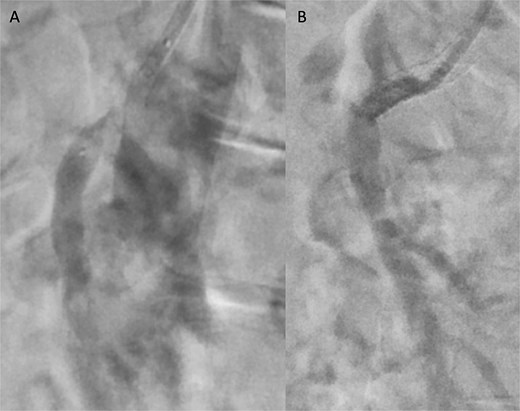

A 76-year-old female patient with a medical history of diabetes mellitus and cholecystectomy presented to the emergency department with a 7-month history of postprandial abdominal pain, food fear, and weight loss (25–30 kg). Over the past 3 days she referred symptom worsening to constant pain. On the physical examination, the abdomen was tender to palpation. Laboratory results revealed leukocytosis (13.700/μl), high C-reactive protein (23 mg/dl) and lactate 0.7 mmol/L. A previously performed computed tomography angiography (CTA) in context of a lithiasic cholecystitis revealed celiac trunk occlusion and pre-occlusive stenosis of the SMA ostium but the patient was not referred for a vascular surgery consultation. A CTA scan obtained in the emergency department revealed thrombotic occlusion of the SMA origin associated with distal embolization (Fig. 1A–C). In this context, the diagnosis of acute-on-chronic mesenteric ischemia was assumed, and the patient was proposed for urgent endovascular revascularization. A 7F (French) sheath was placed via percutaneous access in the left brachial artery, and SMA catheterization was performed using a triaxial system (sheath, MP catheter and Progreat® catheter). Diagnostic angiography confirmed the CT findings (Fig. 2A). Catheter-directed thrombolysis was first performed with a 5 ml bolus of alteplase, followed by percutaneous thrombectomy using the Penumbra® system (Fig. 2B), with retrieval of fresh thrombus (Fig. 3). Primary stenting of the SMA ostium was also performed using an Advanta® 6 × 39 mm stent with proximal flair, with an excellent imagological result (Fig. 4A and B). The postoperative course was uneventful, with significant improvement of symptoms and clinical status. A CTA prior to discharge revealed a patent stent with proper placement and no evidence of residual thrombus (Fig. 5A and B). The patient was discharged on the seventh postoperative day with apixaban 5 mg twice daily. Follow-up of the patient at 6 months revealed that the stent remained patent, with no reported abdominal complaints. The patient gained 15 kg at this point of follow-up.

Angiographic images before (A) and after (B) primary stenting of SMA ostium using a 6 × 39 mm Advanta® stent with proximal flare.